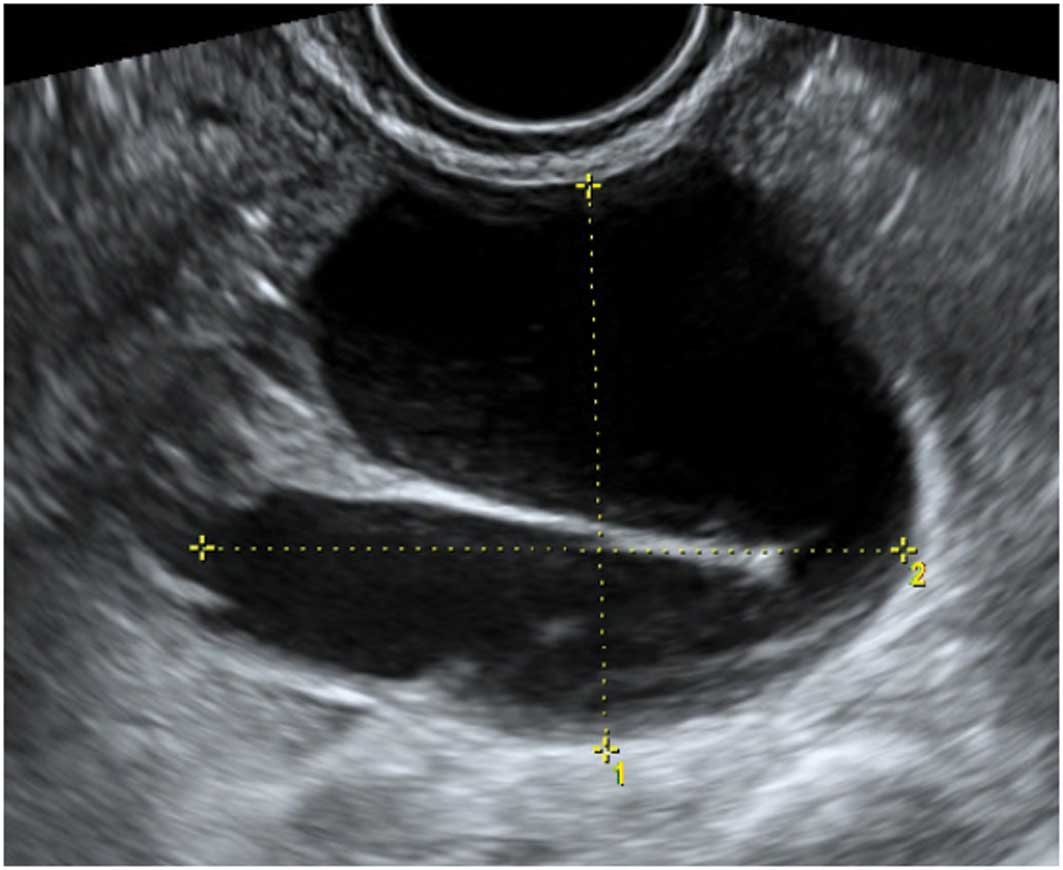

Endometriomas

Ultrasonography is particularly sensitive for accurately diagnosing ‘typical’ endometriomas, most commonly seen in premenopausal women. Typically an endometrioma is a unilocular tumor and has low-level echogenicity representing old blood in the cyst cavity (commonly termed ‘ground glass’). It is this ‘ground glass’ feature that is the most typical feature (28,31–33) (Fig. 15).

Figure 15

Typical endometriomas.

Endometriomas may also have atypical features, and frequently debris within the cyst may give the impression that it is a unilocular-solid lesion with solid papillary projections. In postmenopausal women the appearances of an atypical endometrioma should be examined very carefully as there is a significant risk of malignancy in such lesions in this age group (29,32) (Fig. 16).

Figure 16

Atypical endometriomas with solid papillary projections. (A) Multilocular solid endometrioma. (B) Unilocular solid endometrioma.

During pregnancy endometriomas can change their appearance secondary to decidualization. The features may become quite alarming, with solid vascular projections into the cyst cavity. When no pre-existing scan of the ovary is documented it is difficult in these cases not to suspect malignancy (Fig. 17), although papillary projections were a more frequent sonographic feature among malignant lesions than among benign endometrioid cysts (34,35).